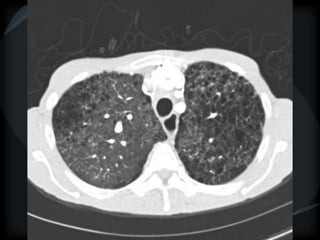

miliary

random